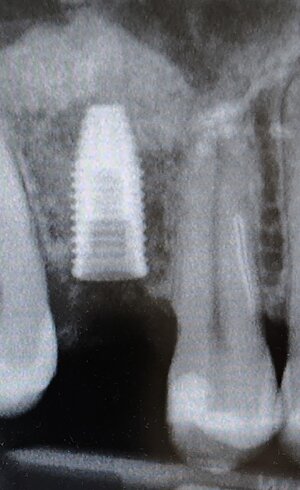

Implantologia Guidata: chirurgia mini-invasiva di alta precisione.